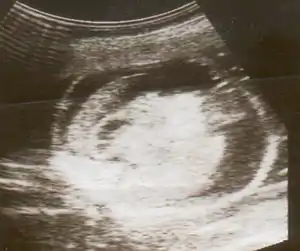

| An ultrasound showing a fetus with hydrops fetalis | |

Hydrops fetalis can be diagnosed and monitored by ultrasound scans.[1] An official diagnosis is made by identifying excess serous fluid in at least one space (ascites, pleural effusion, of pericardial effusion) accompanied by skin edema (greater than 5 mm thick). A diagnosis can also be made by identifying excess serous fluid in two potential spaces without accompanying edema. Prenatal ultrasound scanning enables early recognition of hydrops fetalis and has been enhanced with the introduction of MCA Doppler.[7]